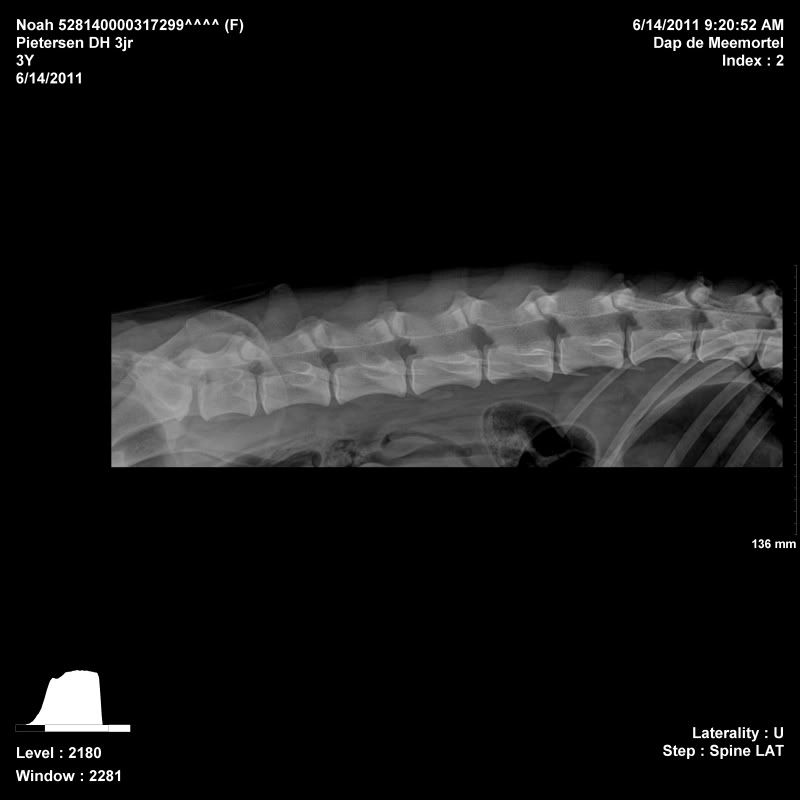

Noah is toen ze 11 maanden gerontged op ellebogen en heupen, dat was toen helemaal goed. Daarna 2 jaar fanatiek gaan sporten (1x in de week flyball, 2x in de week ipo). Voor mijzelf wilde ik graag weten wat 2 jaar sporten voor invloed heeft op de gewrichten, zodoende ben ik vandaag wezen rontgen in Budel. Ze is ook meteen gecastreerd, zodat ze maar 1x onder narcose moest

Haar heupen, ellebogen en rug waren wederom perfect! De DA was te spreken over haar gewrichten

Afbeelding